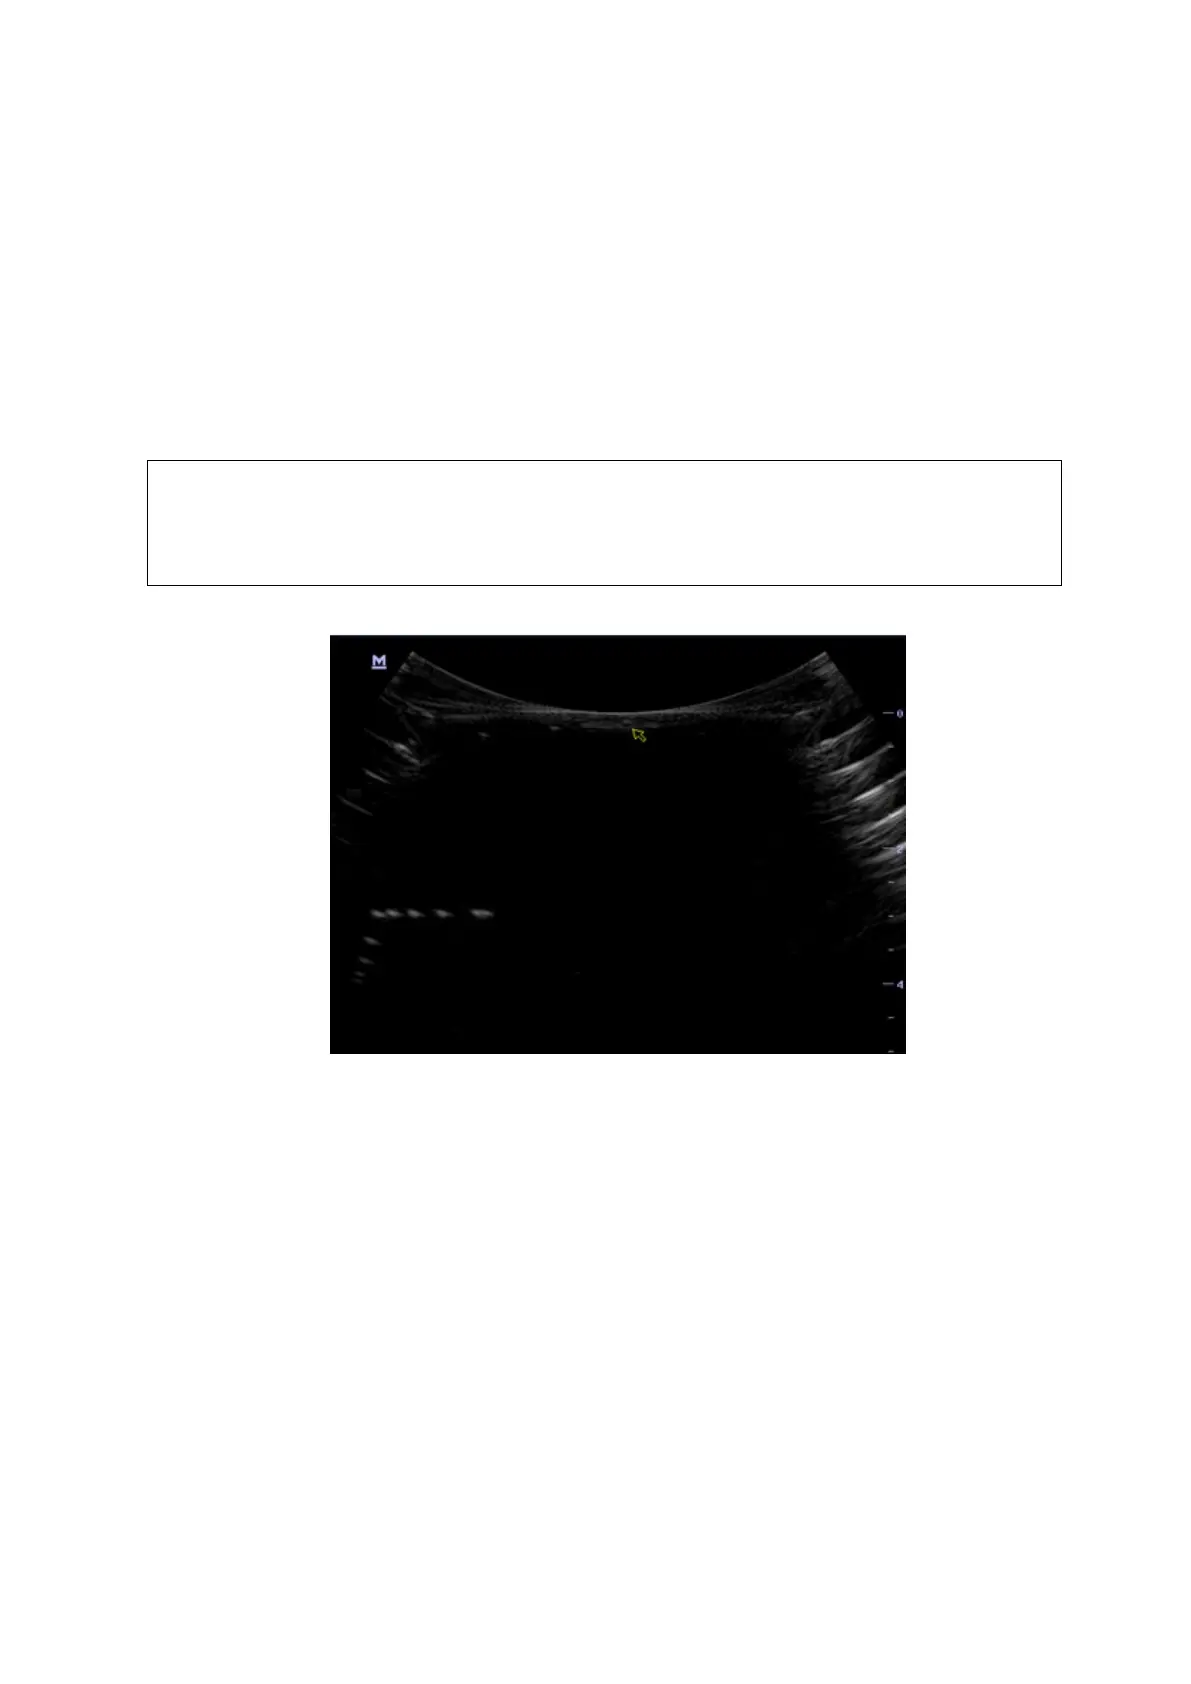

5.5.2.4 Blackout Area

Test Step:

1. Cover the scan surface of the phantom with water or couple gel, gently contact the probe with

the scan surface

2. Adjust the depth at a lower value, and set the focus at the nearest place to the scan surface.

3. Decrease the value of parameters like AP, Gain until the background noise just can be seen.

4. Record the smallest depth of the target that can be seen clearly, that value is the blackout area

value.

As shown in figure below.